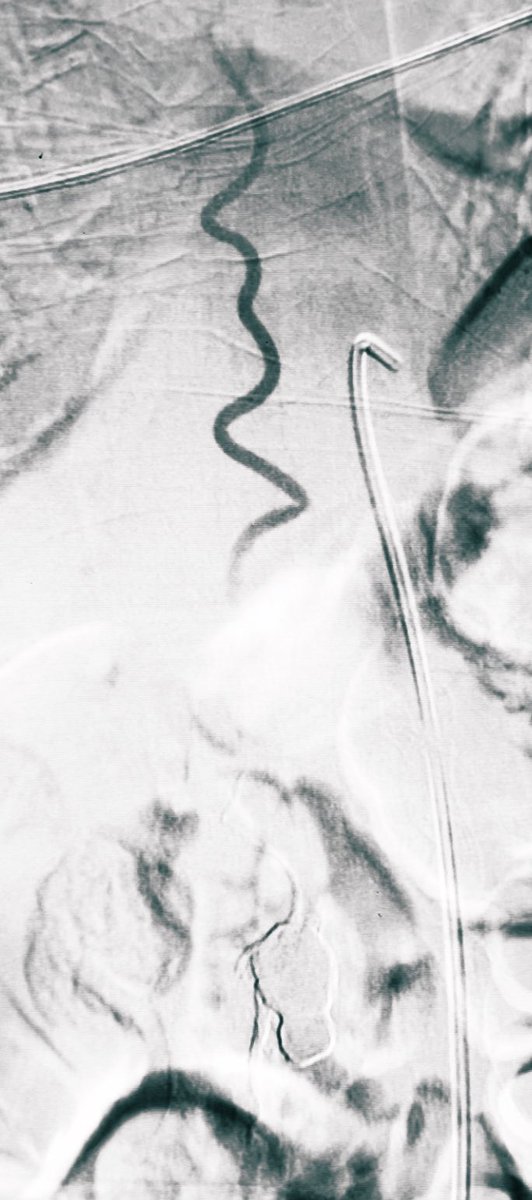

Symptomatic carotid CTO recanalization. 1. SpiderFX serves as both a drill and an embolic protection device. 2. Angioplasty for large-bored aspiration catheter to get through. 3. The aspiration catheter functions as both thrombectomy and exploration of the carotid lumen. 4.

Symptomatic carotid CTO recanalization.

1. SpiderFX serves as both a drill and an embolic protection device.

2. Angioplasty for large-bored aspiration catheter to get through.

3. The aspiration catheter functions as both thrombectomy and exploration of the carotid lumen.

4.